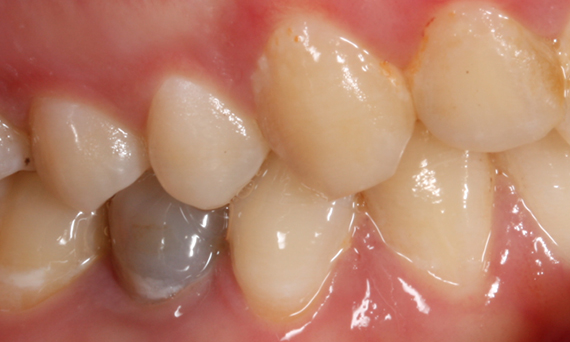

Before: Tooth 24 with horizontal root fracture and peripheral infection.

After: Preservation of esthetics and the natural soft tissue contour.